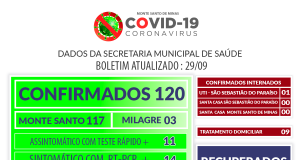

- covid-19

- Destaques Monte Santo de Minas

- Distrito de Milagre